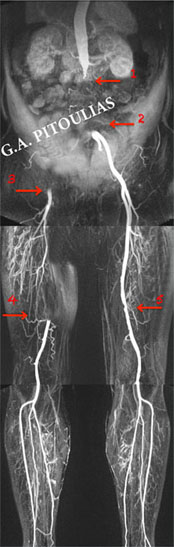

Ο ασθενής υποβλήθηκε και σε μαγνητική αγγειογραφία (δεξιά εικόνα) που έδειξε:

- Πλήρη απόφραξη της αορτής, μετά τις νεφρικές που δεν έχουν στένωση (βέλος 1) και πλήρη απόφραξη των κοινών λαγονίων αρτηριών

ΣΤΗ ΣΥΝΕΧΕΙΑ ΜΕΣΩ ΠΑΡΑΠΛΕΥΡΟΥ ΔΙΚΤΥΟΥ ΕΠΑΝΑΣΧΗΜΑΤΙΖΟΝΤΑΙ

- Η αριστερή κοινή λαγόνιος αρτηρία αμέσως πριν το διχασμό της σε έσω και έξω λαγόνιο αρτηρία (βέλος 2)

- Η δεξιά κοινή μηριαία και η εν τω βάθει μηριαία αρτηρίες  (βέλος 3), ενώ η δεξιά έσω και έξω λαγόνιες αρτηρίες είναι αποφραγμένες

ΣΥΝΥΠΑΡΧΟΥΝ

- Πλήρης απόφραξη της δεξιάς επιπολής μηριαίας σε μήκος 20εκ. και επανασχηματισμός της άνωθεν του γόνατος ιγνυακής αρτηρίας (βέλος 4)

- Διάχυτες μικροστενώσεις της αριστερής επιπολής μηριαίας αρτηρίας (βέλος 5)

- Βατότητα των κνημιαίων αρτηριών αμφοτερόπλευρα